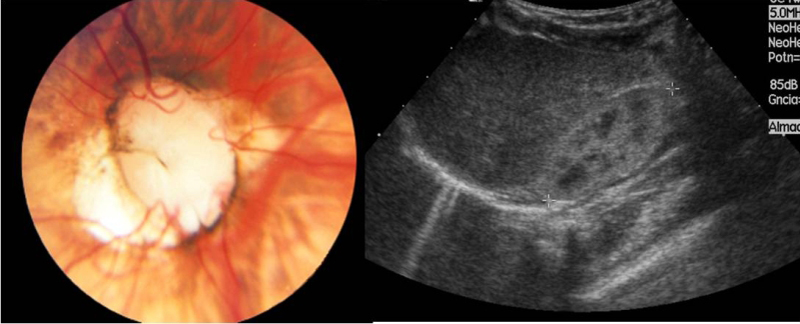

- Pseudopapiledema, drusas del nervio óptico y otras causas

Las drusas son concreciones globulares situadas en la cabeza del nervio óptico que pueden crecer y calcificarse con el paso del tiempo. La TC orbitaria puede mostrar calcificaciones, pero la ecografía ocular es una prueba mucho más sensible y eficaz, por lo que constituye la prueba de elección. El diagnóstico de otras causas de pseudopapiledema (elevación nasal del disco, disco repleto del hipermétrope, tracción hialoidea, presencia de fibras de mielina, tejido glial peripapilar), se realiza con la oftalmoscopía y no está indicado realizar pruebas de neuro-imagen.

- Un caso particular es el de disco óptico vacío (“Vacant disc”). Se presenta de forma bilateral con discos excavados y anomalías en el origen de los vasos centrales en el contexto del síndrome papilorrenal. No requiere neuroimagen, pero sí la realización de una ecografía doppler renal para el estudio de anomalías estructurales en el aparato urinario como la hipoplasia renal (Figura 9).